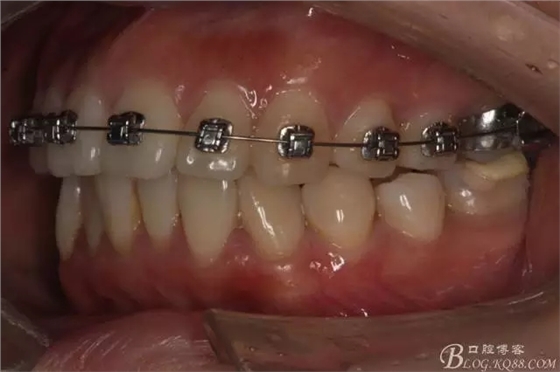

該病例主要為17、27頰側(cè)位同時(shí)伴有伸長(zhǎng),當(dāng)然種植支抗可以解決,但還有簡(jiǎn)單實(shí)用的辦法嗎?如圖,在橫腭桿遠(yuǎn)中延伸出牽引鉤,位置盡量遠(yuǎn)離合平面,7粘舌側(cè)扣,牽引力的方向?yàn)閴旱图吧嘞?,下圖為兩個(gè)月的效果,17已到位,27還未到位。